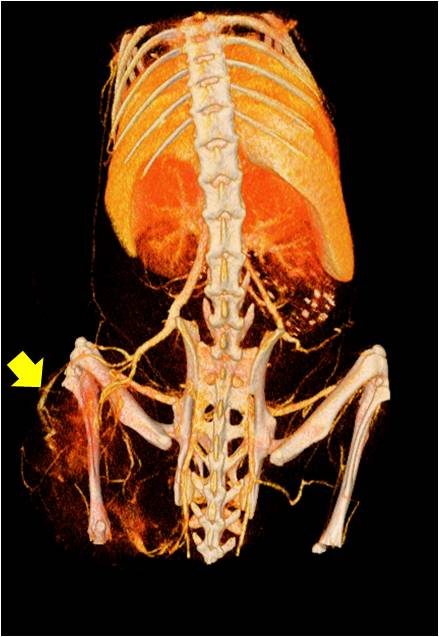

心血管

胸部和心血管的層析成像 胸部和心血管的3D圖像